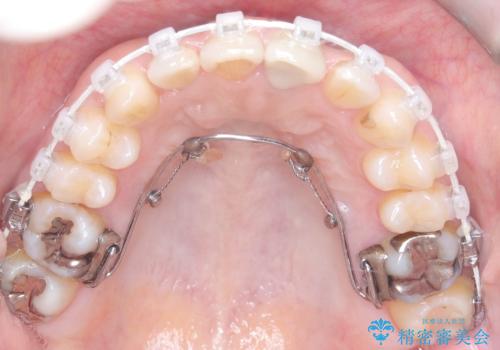

スペースを確保するために抜歯を行う選択肢もありましたが、歯列の幅や骨格とのバランスから判断し、上顎の奥歯を後方に移動させることでスペースを作る方針を立てました。そのため、まずリンガルアーチ(内側に装着する固定式装置)を用いて奥歯を遠心移動させ、その後ワイヤー矯正で歯列全体を整える治療計画を立案しました。

初期段階では、リンガルアーチを上顎に装着し、奥歯を少しずつ後方へ移動させていきました。これにより前歯部の歯列に十分なスペースを確保。その後、マルチブラケット(ワイヤー矯正)を用いて、突出した八重歯を正しい位置に誘導しながら、歯並び全体を整えていきました。

治療中は咬合バランスや歯列の中心(正中)の位置にも注意を払い、最終的には上下の正中が一致し、左右の臼歯関係も理想的な形に改善されました。見た目の変化はもちろん、かみ合わせの安定や清掃のしやすさも向上。